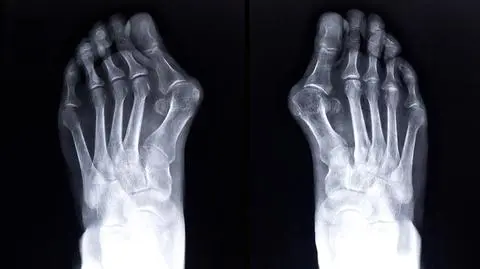

- Ta deformacja stopy polega na odchylaniu się palucha w kierunku pozostałych palców - wyjaśniał. Charakterystyczna kostka, która wydaje się być czymś, co wyrosło, w rzeczywistości nie jest żadną naroślą. - W tym miejscu nic nie wyrasta - podkreślił dr Kołodziejski. - To, co my widzimy, jest prawidłowym kształtem głowy pierwszej kości śródstopia, która się przemieściła tylko dlatego, że paluch uciekł w kierunku bocznym a stopa uległa rozpłaszczeniu poprzecznemu - wyjaśniał.

- W naturalnej stopie dochodzi do przenoszenia obciążenia przez głowę pierwszej i piątej kości śródstopia oraz przez piętę - wyjaśniał. - W przypadku haluksów dochodzi do rozwoju płaskostopia poprzecznego, czyli przenoszenie obciążeń zachodzi przez drugą i trzecią kość śródstopia, które są kompletnie do tego nieprzystosowane - podkreślił.